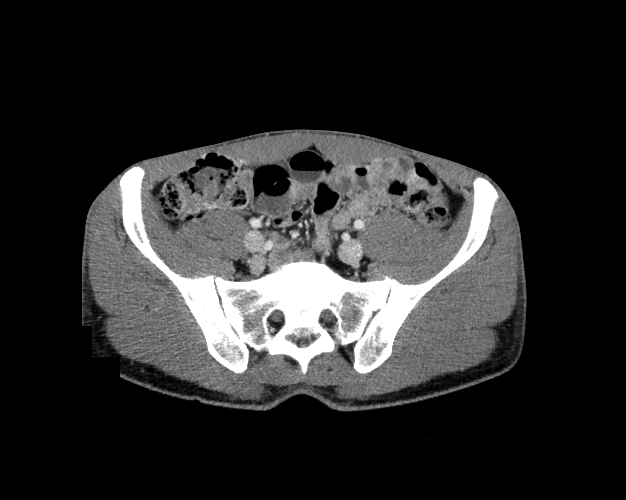

Body

Covers abdominal CT anatomy.